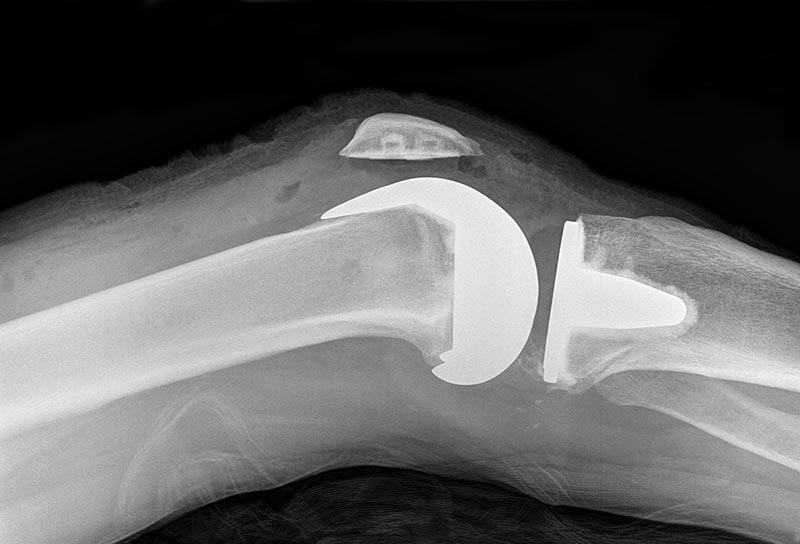

Major surgery: After I’d been numbed completely from the waist down, Dr. Scheffer opened up my right leg with an eight-inch incision, dismantled my knee, and then rebuilt it with new parts, way after-market. First, he sawed off 10 millimeters (about 3/8 of an inch) of the bottom of my femur and the top of my tibia. And it wasn’t gentle: I heard what sounded like a Sawzall through the haze. After another 10 mm was removed from the inside of my kneecap, three replacement parts were cemented into place, and then I was cleaned up, sewn up, and glued up — all in an hour. My femur and tibia needed size 8 replacement components, while my patella called for a size 41. OK,…